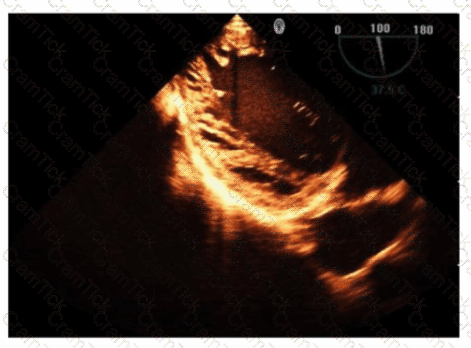

What is the incidental finding seen by color Doppler in this four-chamber view of a patient with left atrial enlargement?

Which view best demonstrates a wall thickening abnormality of the apical lateral segment?